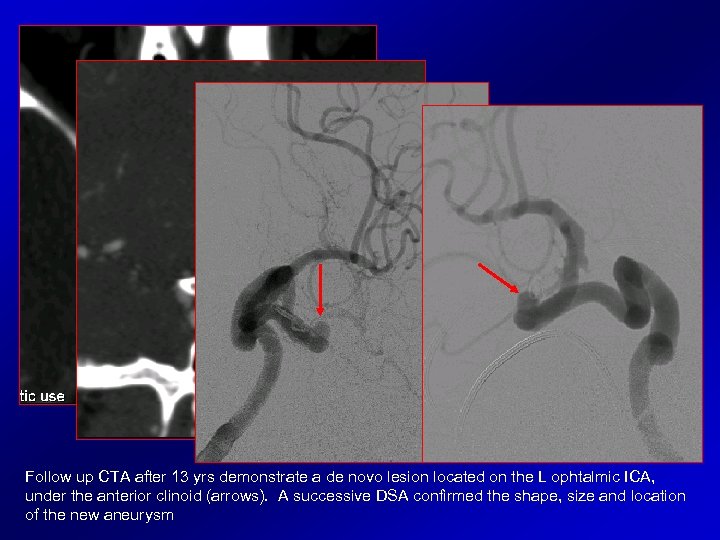

Follow up CTA after 13 yrs demonstrate a de novo lesion located on the L ophtalmic ICA, under the anterior clinoid (arrows). A successive DSA confirmed the shape, size and location of the new aneurysm